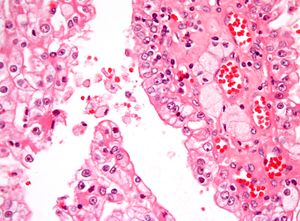

The most common type of kidney malignancy is renal cell carcinoma,[11] which is thought to originate from cells in the proximal convoluted tubule of the nephron.[9][12] Another type of kidney cancer although less common, is transitional cell cancer (TCC) or urothelial carcinoma of the renal pelvis.[13] The renal pelvis is the part of the kidney that collects urine and drains it into a tube called the ureter.[13] The cells that line the renal pelvis are called transitional cells, and are also sometimes called urothelial cells. The transitional/urothelial cells in the renal pelvis are the same type of cells that line the ureter and bladder. For this reason TCC of the renal pelvis is distinct from RCC and is thought to behave more like bladder cancer.[13] Other rare types of kidney cancers that can arise from the urothelial cells of the renal pelvis are squamous cell carcinoma and adenocarcinoma.[9]

Renal cell carcinoma has been further divided into sub-types based on histological features and genetic abnormalities. The 2004 WHO Classification of the Renal Tumors of the Adults describes these categories:[17]

- Clear cell RCC